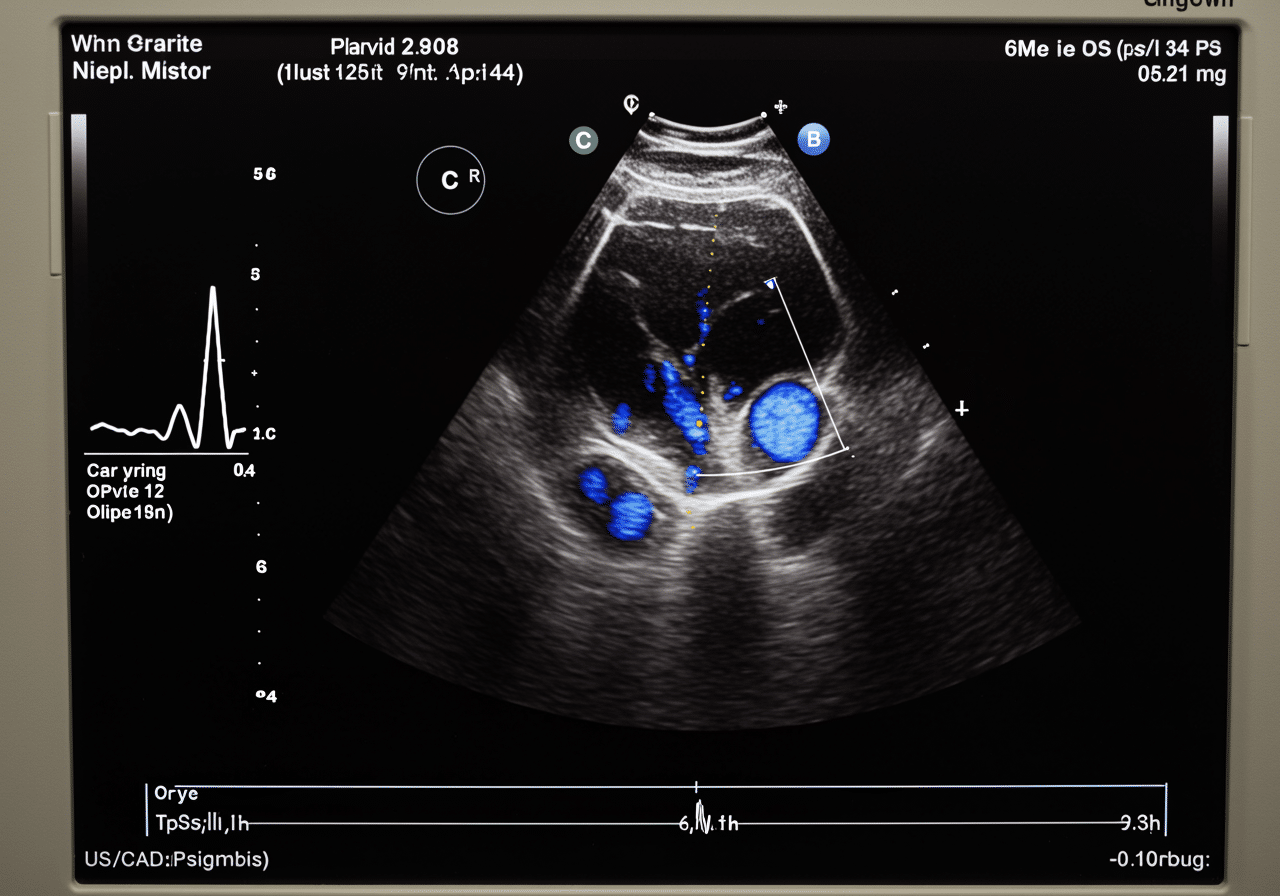

Vascular Doppler Process at Priority ER: Zero Wait Diagnostic Imaging

Upon arrival at Priority ER for vascular doppler ultrasound for deep-vein thrombosis services, patients bypass traditional triage delays through our zero-wait protocol. Board-certified emergency physicians trained in vascular imaging begin assessment immediately, utilizing duplex doppler technology that produces high-resolution blood flow images in seconds rather than minutes[9]. This comprehensive approach identifies clot patterns that general urgent care facilities might miss, such as proximal DVT or floating thrombi requiring specialized anticoagulation protocols.

Advanced Vascular Doppler Technology: Beyond Basic Urgent Care

Priority ER's diagnostic capabilities for vascular doppler ultrasound for deep-vein thrombosis exceed Joint Commission standards for emergency departments[14], featuring equipment typically found only in specialized vascular centers. Our duplex doppler system produces images with 30% better resolution than standard urgent care facilities, enabling detection of small thrombi, valve incompetence, and venous obstruction as subtle as 1mm[15]. The integration of PACS (Picture Archiving and Communication System) technology allows instant image transmission to consulting vascular surgeons when complex DVT requires specialized anticoagulation planning.

Advanced imaging through our 64-slice CT scanner provides three-dimensional venous reconstruction within minutes, crucial for identifying clot extent, pulmonary embolism risk, and treatment requirements that standard doppler cannot fully assess. For chest pain cases with leg swelling, our digital imaging system captures both pulmonary and venous studies simultaneously, reducing radiation exposure by 40% while providing comprehensive thrombosis evaluation. This technology gap explains why the American College of Emergency Physicians recommends freestanding ERs over urgent care for all suspected DVT and serious vascular emergencies requiring immediate diagnostic imaging.